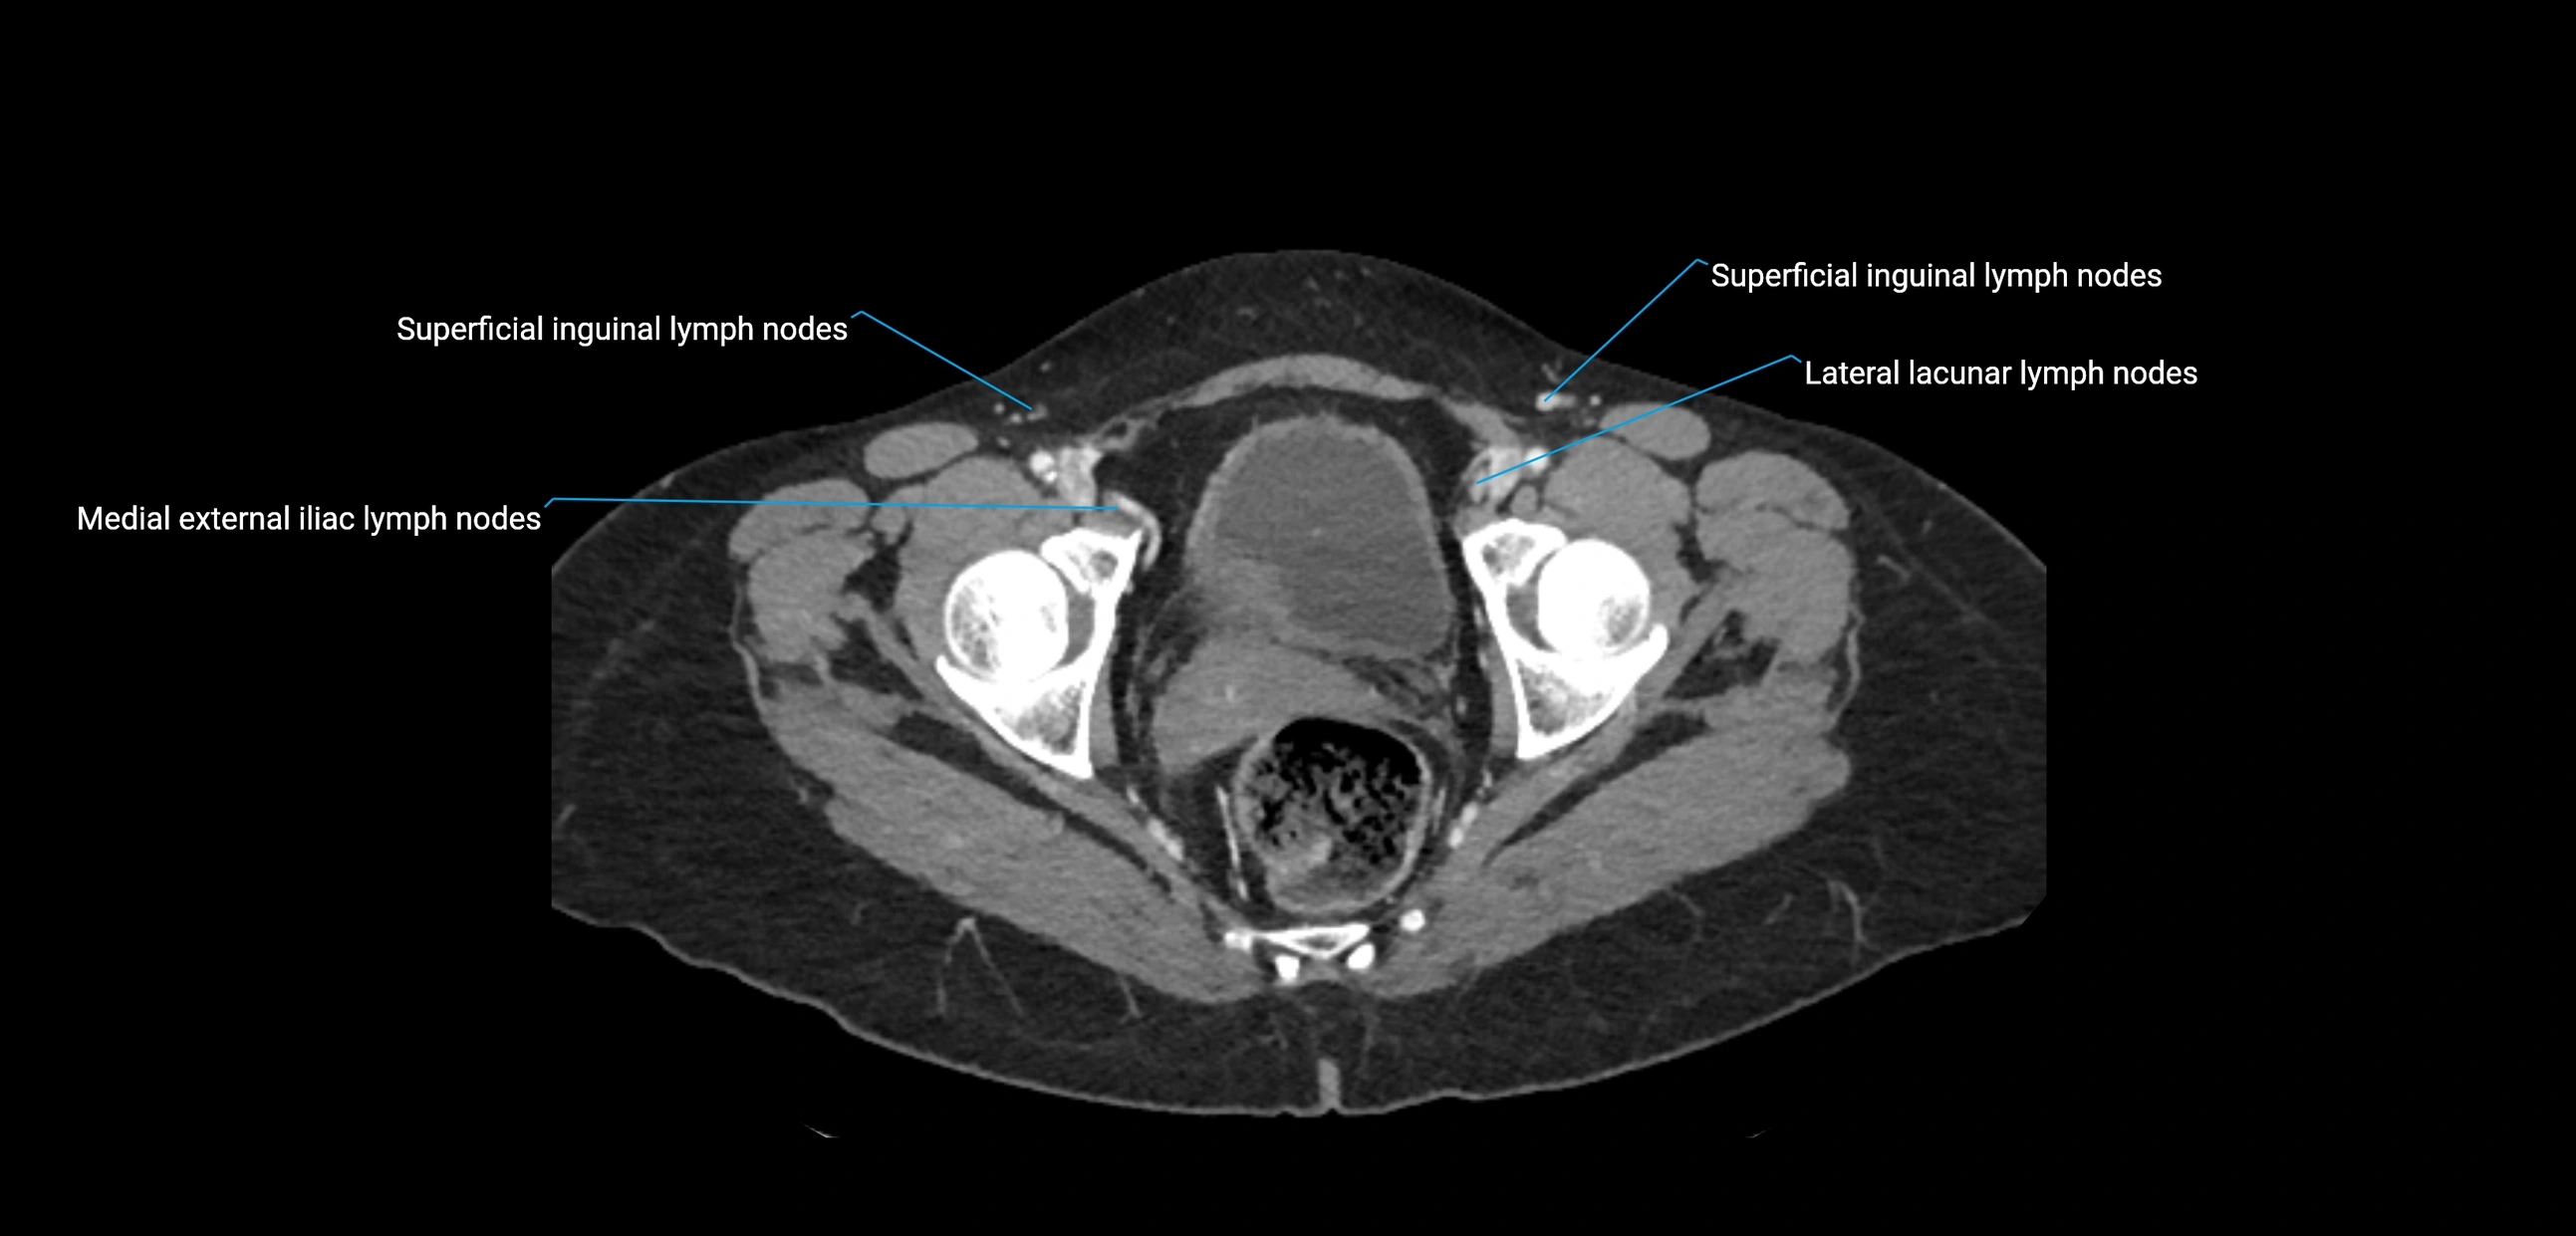

CT Appearance

CT Pre-Contrast:

• Nodes appear as soft-tissue density nodules adjacent to the aorta and IVC

• Calcification may be seen in chronic infections (e.g., tuberculosis)

CT Post-Contrast:

• Normal nodes enhance homogeneously

• Malignant nodes may show heterogeneous enhancement, central necrosis, or conglomerate formation

• Size >1 cm short axis is suspicious, though morphology and distribution are equally important

CT Venography (CTV):

• Demonstrates nodal encasement or compression of adjacent vessels (aorta, IVC, renal veins)

• Useful in staging testicular and ovarian malignancies

• Provides 3D reconstructions for retroperitoneal lymph node dissection planning

CT image

image